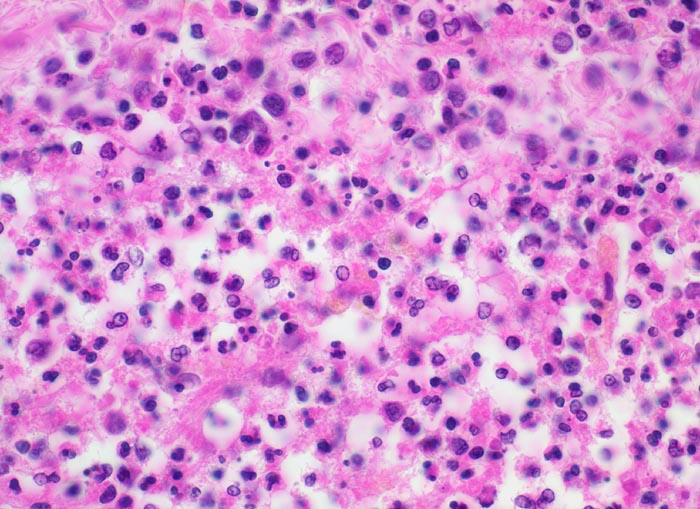

Eitrige Meningitis

Meningen

Zytologisch finden sich mehr als 90% neutrophile Granulozyten, ausserdem Fibrin, Makrophagen, degenerierende Zellen, Zelldetritus und manchmal Mikroorganismen. Nach Beginn der Antibiotikatherapie kommt es zu einem raschen Abfall der Zellzahl. Die neutrophilen Granulozyten degenerieren und aktivierte Monozyten beherrschen das Zellbild. Plasmozytoide Lymphozyten und Plasmazellen können dazukommen. In der Reparationsphase verschwinden die Granulozyten, die Anzahl Plasmazellen verringert sich, die Makrophagen sind degeneriert und haben vakuolisiertes Zytoplasma.